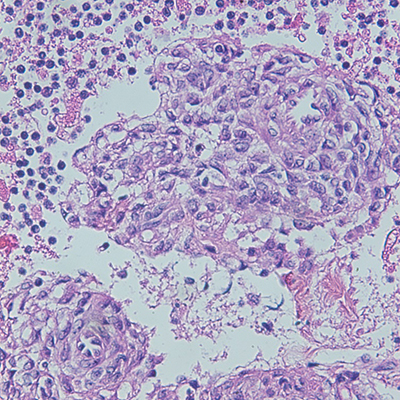

The surgical resection of the cyst wall showed proliferation of spindled cells surrounding thin-walled vessels and prominent cystic spaces (Figure 2). The cells lacked atypia and mitotic activity. Some of the cells had elongated, cigar-shaped nuclei with eosinophilic cytoplasm, reminiscent of smooth muscle cells. Others were ovoid to cuboidal, with focal clear cell changes. Aggregates of lymphocytes were also noted on surgical resection. The presence of prominent cystic spaces and the bland appearances of epithelioid cells surrounding vessels raised the possibility of perivascular epithelioid cell tumor (PEComa)/lymphangioleiomyomatosis (LAM). Differential diagnosis includes other low-grade spindle neoplasms and epithelial neoplasms. Immunohistochemical stains were ordered. The epithelioid cells stained positive for SMA, desmin, caldesmon, HMB-45, and TFE3, negative for CK7, CK20, PAX8, WT1 (ruled out epithelial origin), negative for DOG1 (ruled out gastrointestinal epithelial tumor), negative for STAT 6 (ruled out hemangiopericytoma), and negative for CD34 (ruled out spindle cell lipoma), supporting the diagnosis of PEComa. LAM should also be considered in this young female patient with history of abnormal lung imaging (see discussion below).

Figure 2: Cyst wall resection. A: Spindled cell proliferation in cystic spaces, H&E, 4x. B: Spindled cells with adjacent aggregates of lymphocytes, H&E, 20x. C: Spindled cells surrounding vessel, H&E, 40x. D: Spindled cells surrounding multiple vessels, H&E, 60x. E: Spindled to epithelioid nuclear shapes, H&E, 60x. F: SMA IHC, 20x. G: HMB45 red IHC, 20x. H: TFE3 IHC, 20x.